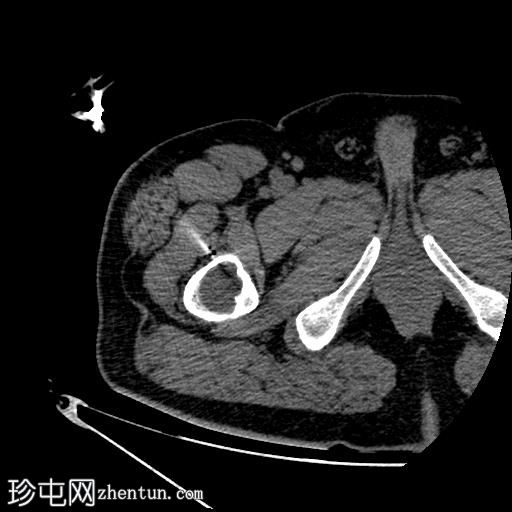

轴位

平扫

右股骨近端干骺端,股骨大转子下方可见一边界清晰的溶骨性病变。

未见皮质破坏及骨膜反应。

根据CT影像学表现和组织病理学结果,应考虑右股骨干近端良性囊性骨病变。